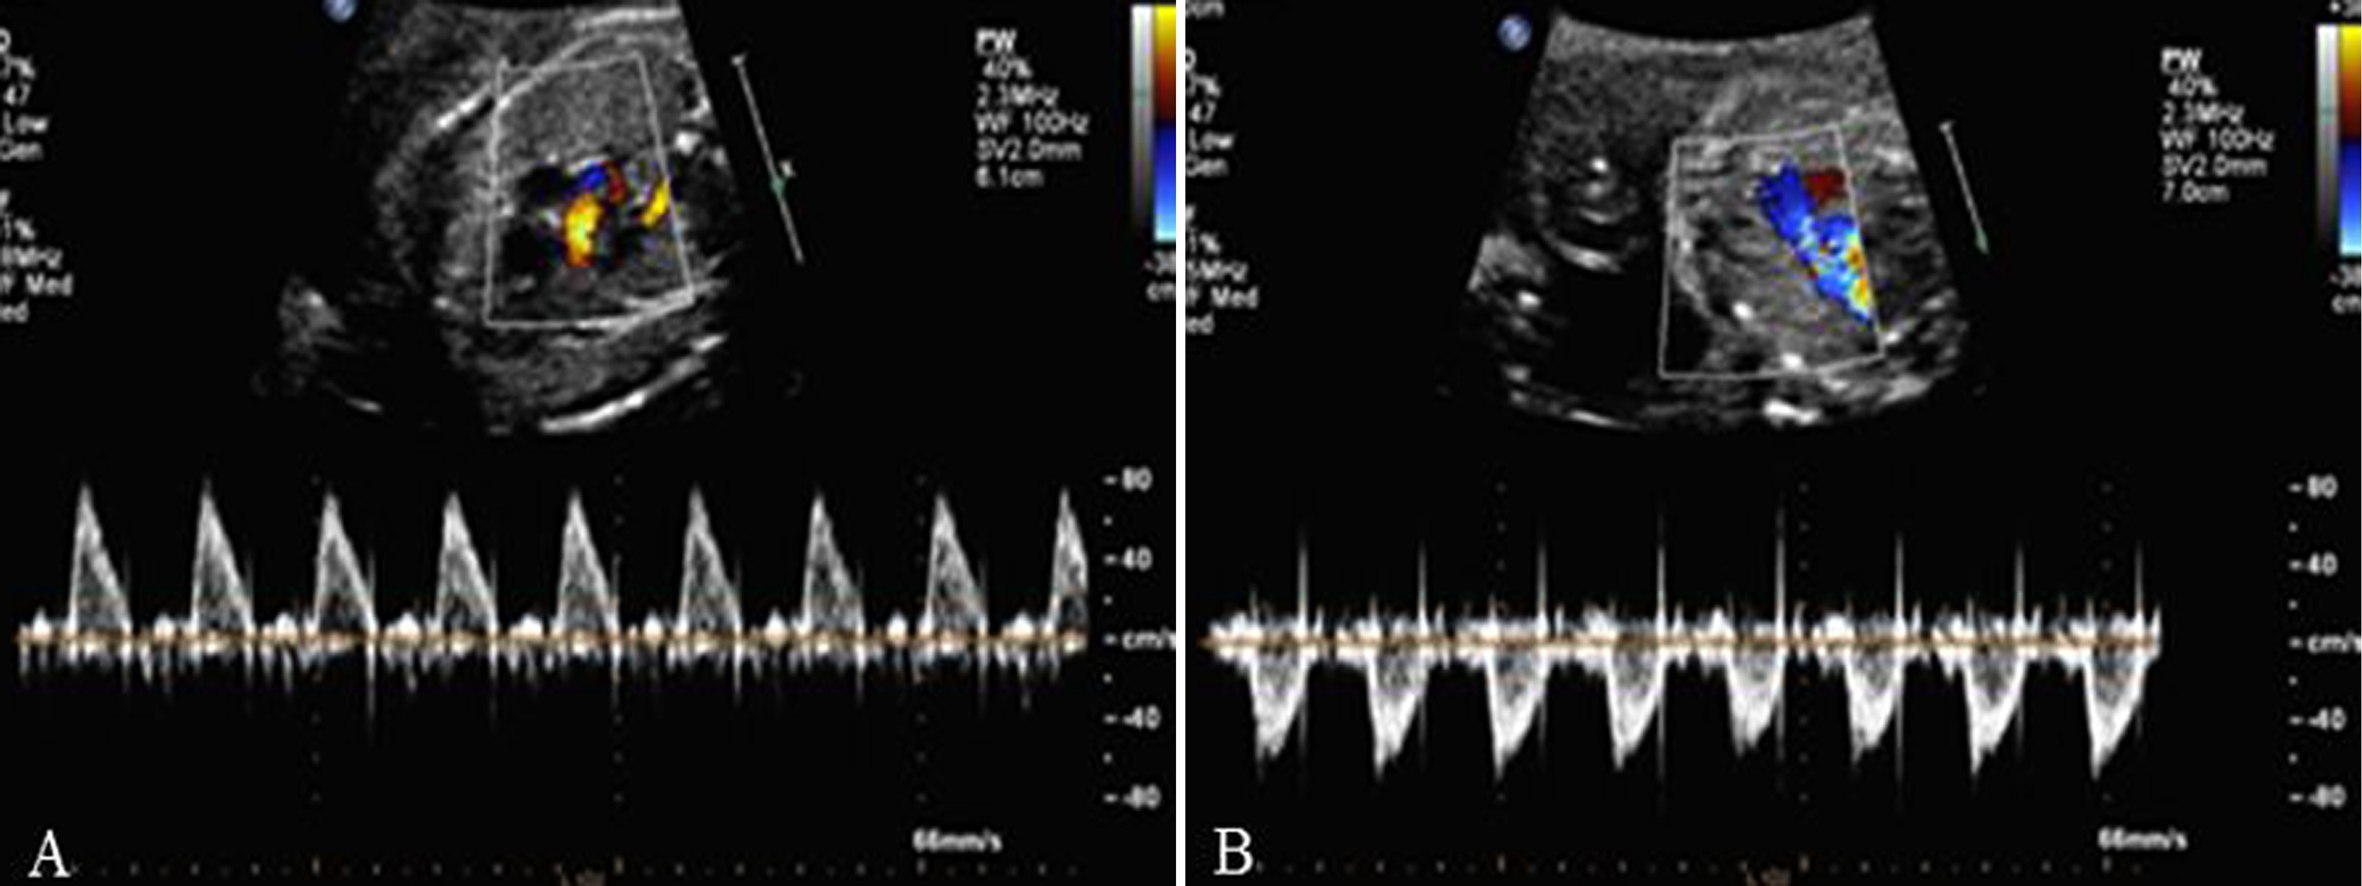

2.检查内容 观察彩色多普勒显示的过房室瓣、半月瓣、卵圆孔瓣的血流及各血管内(包括上下腔静脉、肺静脉、主动脉、肺动脉、主动脉弓、动脉导管弓、静脉导管等)的血流方向是否正常,有无反向血流或五彩缤纷、色泽镶嵌的高速血流信号显示。用脉冲多普勒测量过房室瓣、半月瓣血流、测量静脉导管内血流,以了解胎儿心脏节律情况、分析心房舒缩与心室舒缩之间的关系、了解胎儿的心功能等。正常胎儿房室瓣多普勒血流时间流速曲线呈双峰频谱,E峰小于A峰(图1);有时,三尖瓣血流可表现为单峰见切迹。半月瓣血流均呈单峰,多普勒时间流速曲线图显示肺动脉瓣血流收缩期射血时间大于主动脉瓣,峰值上升支亦快于主动脉(图2)。静脉导管为连接脐静脉和下腔静脉间的一段很短的血管,直径约为1~2mm,应用彩色多普勒可发现脐静脉血流至此处时,流速增快,呈花色血流信号(图3)。正常胎儿静脉导管的血流频谱呈连续单向双期双峰血流频谱, 有两个波峰两个波谷,第一个波峰“S”峰(房室瓣的关闭下移导致心房压的下降),第二个波谷“V”谷(心室等容舒张房室瓣上移导致暂时的心房压上升),第三个波峰“D”峰(为心室舒张房室瓣开放,血流快速流入心室导致心房压下降),第四个波谷“A”谷(心房收缩)(图4)。

图2主动脉血流时间流速曲线(A)和肺动脉血流时间流速曲线(B)